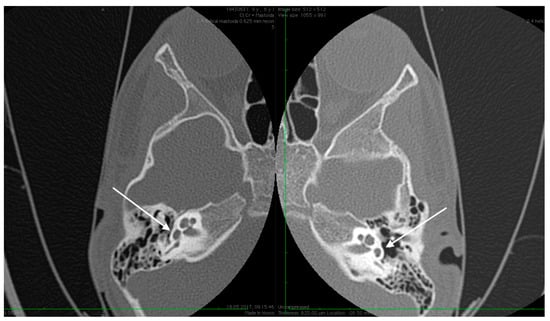

Figure 2.

High resolution axial CT scan of left temporal bone showing a missing oval window and stapes suprastructure (arrow) on both sides.

Abnormal position of the facial nerves in their mastoid segment, bilaterally (arrows).